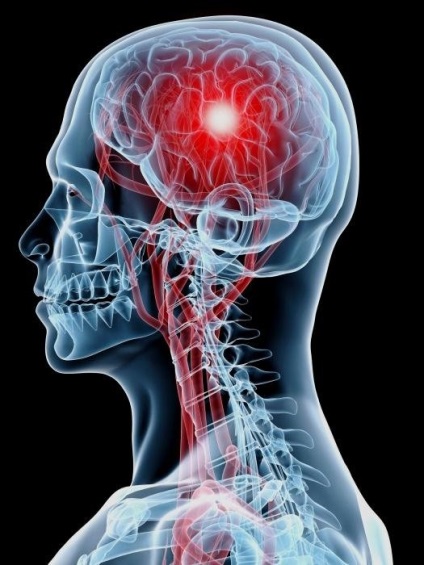

Stroke - állapot az úgynevezett „sürgősségi kóros eltérések”, állapította meg, hogy szükség van a lehető leghamarabb, hogy segítsen, amely nem csak a harc a tüneteket, de gyakran a műtét. Ez a betegség gyakran igényelnek műtéti kezelési módszer, mert megszünteti az ok nem mindig lehetséges gyógyszerek.

Agyvérzés befolyásolja az erek az agy, ami oda vezethet, hogy a nem kívánt következményeket, például bénulás, beszédzavar, légzés, és akár halált is okozhat.

Ha a löket kiváltott hajó törés és vérzés az agyban, csak trepanation ad esélye megtakarítás a betegnek. Csak amikor elérte előtt a kandalló problémák minőségileg megoldani.

agyi vérömleny - patológia felhalmozódása által okozott vér egy korlátozott területen a koponyaüregbe. Haematoma elosztva a nézetet, helyét és méretét, de ezek mind társított törés a véredények és a vérzés.

Trepanation ebben az esetben van szükség annak érdekében, hogy vért kimutatni a problémás területeket, és hozza megfelelő formában. A vérzés lehet állítani más módon, de következményeinek felszámolása az incidens nem mártva a koponyaüreg, ez lehetetlen.